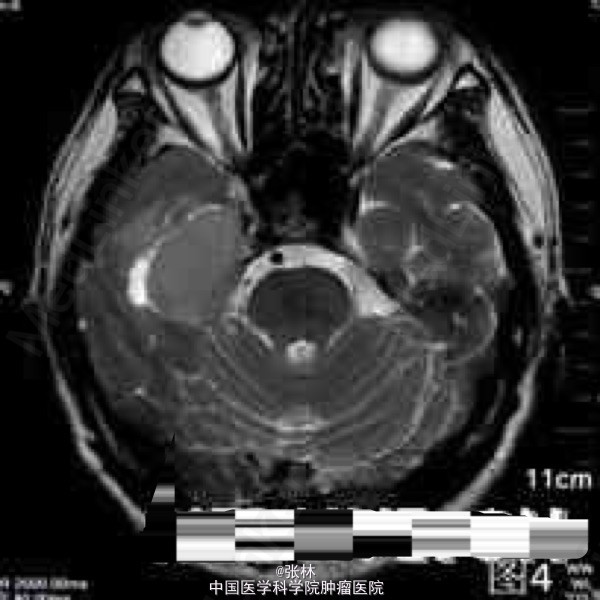

CT表现:右侧颅中窝可见一不规则肿块,呈等密度,内部密度均匀,CT值约37HU,肿块边界尚清晰,略成分叶状,与邻近骨质呈广基底相连,最大截面3.3cm×3.8cm,边缘处可见带状低密度影,边界清晰,CT值约16HU。肿块周边脑组织水肿,密度略减低。肿块周边骨质未见增厚硬化或变薄等异常改变(图1-2)。 CT诊断:右侧颅中窝肿块,伴周围脑组织水肿,建议进一步检查。 MRI表现:右侧颅中窝可见一不规则肿块,最大截面3.6cm×4.1cm,肿块边界清晰,成分叶状,与邻近骨质呈广基底相连(图5-6),在T1WI上呈等信号,在T2WI上呈略高信号;肿块边缘可见不规则液性信号带,在T1WI上呈低信号,在T2WI上呈高信号,与脑组织分界清楚(图3-4);肿块前方颞叶部分脑组织可见片状异常信号,在T1WI上呈稍低信号,在T2WI上呈略高信号,边缘模糊(图3-4);注射对比剂后,肿块实性部分明显强化,并可见“脑膜尾征”,而液性信号带未见强化(图5-6),肿块前方颞叶的片状异常信号未见强化。 MRI诊断:右侧颅中窝脑膜瘤,部分囊变,伴周围脑组织水肿。 手术病理结果:非典型性脑膜瘤,WHO分级II级。 讨论: 脑膜瘤是颅内仅次于胶质瘤的常见原发肿瘤,发病率占颅内肿瘤的16%~17%,在颅内脑外原发肿瘤中占第一位。它起源于脑膜的蛛网膜内皮细胞,常见于富含蛛网膜颗粒与蛛网膜绒毛的地方,以上矢状窦旁、大脑凸面、大脑镰、蝶骨嵴、鞍结节、嗅沟、小脑桥脑角区及小脑幕等部位多见。